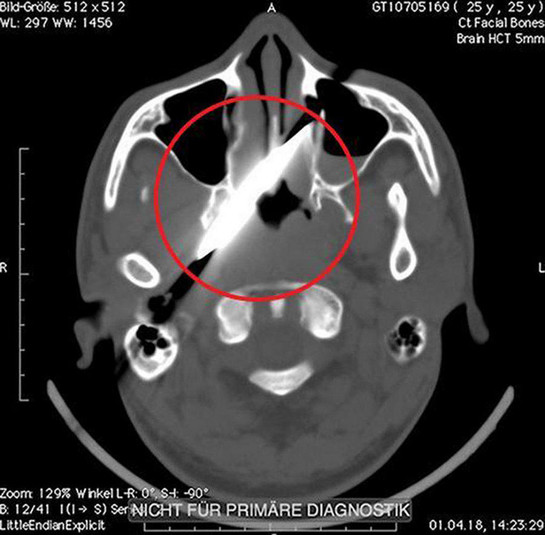

Рентген показав, що ніж зайшов на 10 см в голову, але не зачепив жодної артерії

Удар ножем в око він отримав під час п'яної бійки в барі. Після цього потерпілий як ні в чому не бувало відправився додому спати. Наступного дня чоловікові все ж довелося відвідати медичний заклад. Леза він не помітив, однак голова і очі дуже боліли. Рентген показав, що ніж зайшов на 10 см в голову, але не зачепив жодної артерії. Лікарі навіть вирішили перенести операцію на чотири дні, поки оформлялися необхідні документи.